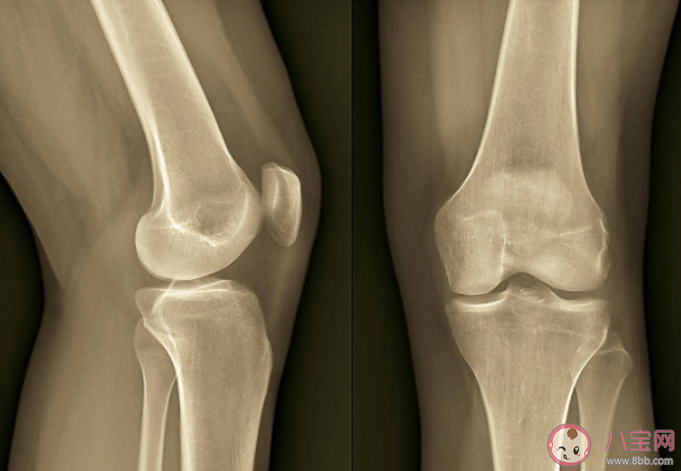

隨著年齡增大,很多老人會出現關節炎問題,空調不是病因,但「冷」可能會加重疼痛感。

有肩周炎、老寒腿等關節不好的人,長時間在低溫的空調房間,比如10~17攝氏度,身體里面TRPA1通道開啟,而這種通道的激活在炎癥的疼痛中很重要。

炎炎夏日,感覺風都帶著熱氣,吹空調是夏日里比較舒服的事情,但也因為吹空調很多人出現了關節疼痛、怕涼的表現,并不一定是風濕性疾病,但可能是風濕性疾病的發病誘因,建議大家科學、舒服的吹空調: